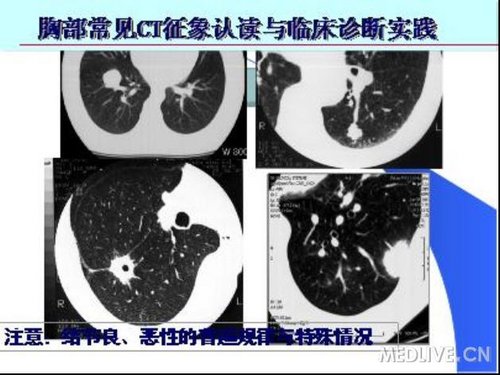

CT征象五:结节与肿块

肺孤立结节(SPN)是:肺实质内一个不伴有肺门或纵隔淋巴结肿大、肺不张或肺炎的圆形或卵圆形致密影,直径2.0cm,有足以测量其直径的、有一定锐利度的边缘,病变内可有钙化或空洞。直径>2.0cm者称为肿块。

肺结节/肿块——单发或多发;良性与恶性。

小结节良性可能性大,较大结节则倾向恶性

直径<5mm结节仅1%为恶性(动态观察)

直径5~10mm者25%~30%为恶性